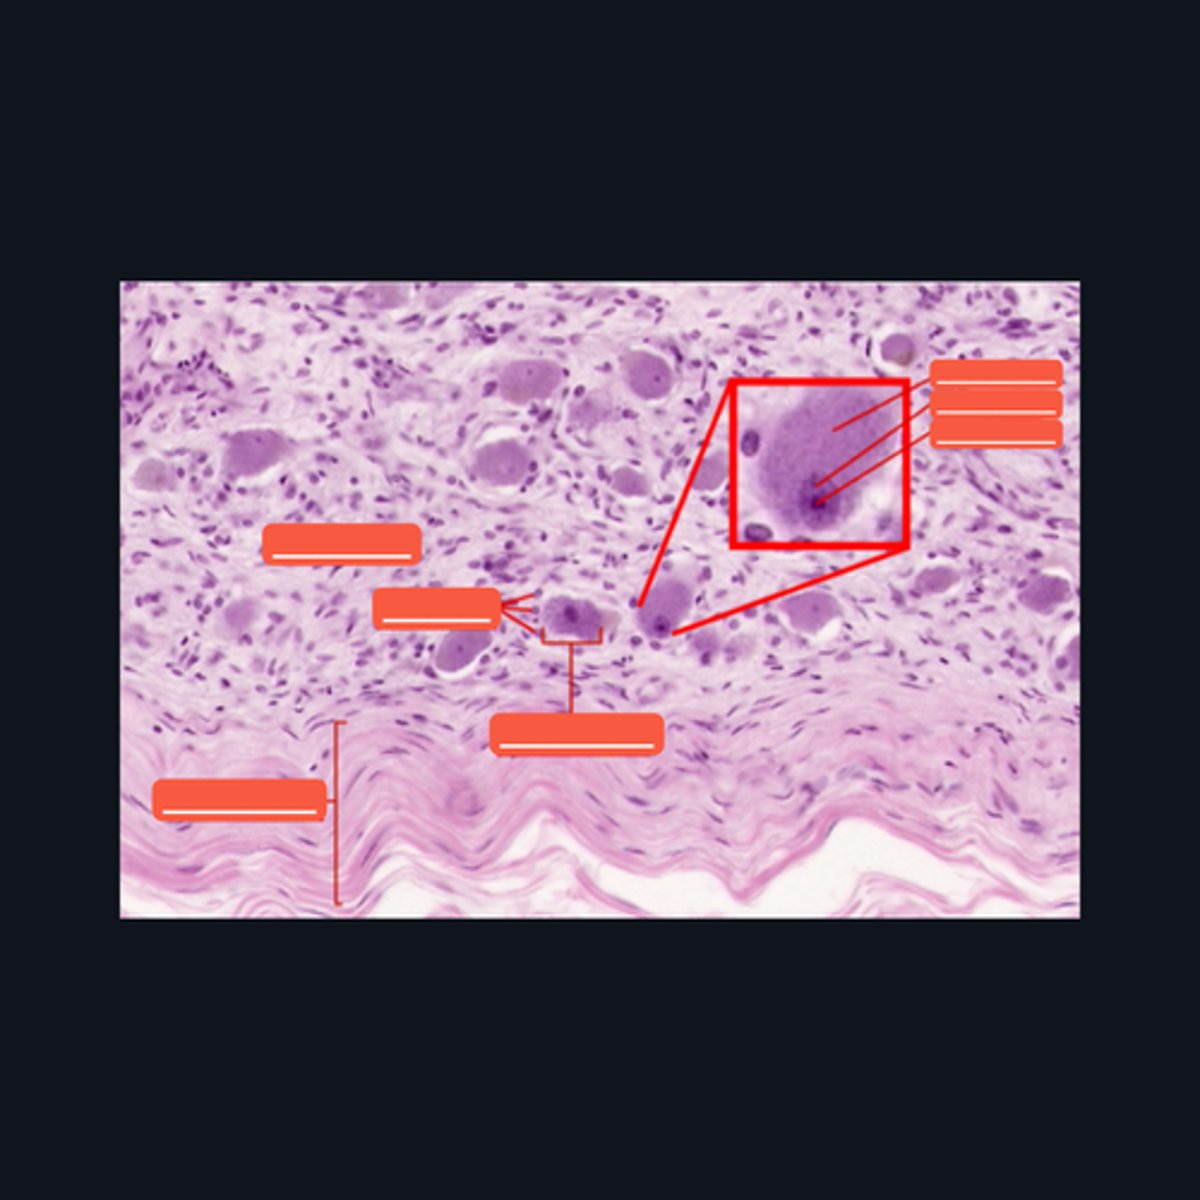

Mucosa, Submucosa, Muscularis Externa

Identify the histologic layers of the digestive tract

(1) Visceral Efferent Neuerons/ Autonomic Ganglion Cells

(2) Meissner's Plexus and Auerbach's Plexus

Cells from the division of the nervous system that innervates this specimen are made up of (1)_______, and whose cell bodies and fibers form (2) two ganglionated plexuses named: _______ and ________.

Submucosa

Identify the pointed histologic layer of the digestive tract

Muscularis Externa

Identify the pointed histologic layer of the digestive tract

Serosa

Identify the pointed histologic layer of the digestive tract

Meissner's corpuscle, Lamellar cells, and Capsule

Identify each pointed structures.

Pacinian corpuscle, Supporting cells, Axon

Identify the pointed structures.